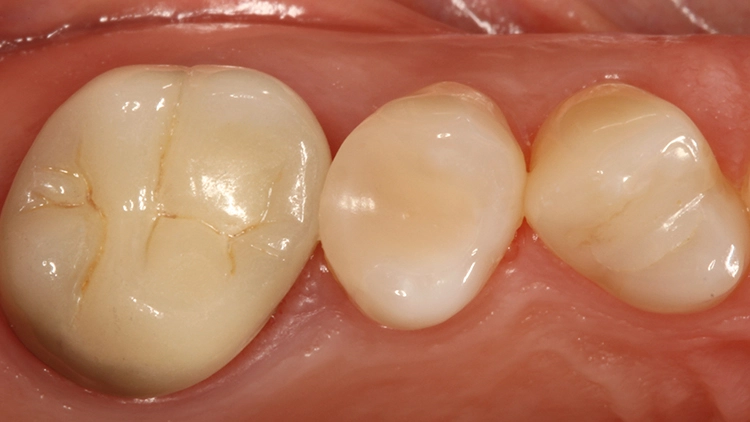

Die Abbildungen 18 und 19 zeigen dieselbe Situation nach 2 Jahren, die Abbildungen 20 und 21 nach 5 Jahren und die Abbildungen 22 und 23 nach 11 Jahren. Die direkte Kompositrestauration zeigte sich im gesamten Beobachtungszeitraum nahezu unverändert; es haben sich lediglich etwas Zahnsteinauflagerungen approximal gebildet, die im Rahmen der demnächst geplanten PZR beseitigt werden. Beim Nachkontrolltermin nach 11 Jahren wurde zudem eine erneute Röntgenaufnahme angefertigt (Abb. 24).

Gut erkennbar sind hingegen die perfekte Randdichtigkeit der Venus Diamond-Restauration an Zahn 25 und die sehr gute Röntgenopazität. Somit konnten dem inzwischen 11 Jahre alten Inlayersatz in direkter Technik mit Komposit durchweg gute Noten vergeben werden. Auch die Patientin zeigte sich mit der Versorgung nach wie vor sehr zufrieden – sie sah ihre damalige Entscheidung zu Gunsten der direkten Versorgungsvariante bestätigt.